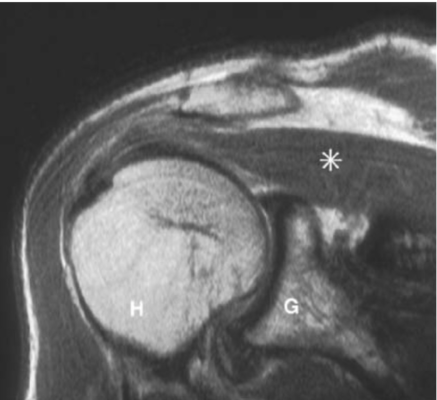

Khoảng dưới mỏm cùng vai:

- có bao hoạt dịch dưới mỏm cùng vai

- Động (dynamic): các cơ, đặc biệt là cơ chụp xoay (rotator cuff). Các thành phần của chụp xoay bao gồm cơ dưới vai, cơ trên gai, cơ dưới gai, cơ tròn bé giúp giữ vững khớp ổ chảo-cánh tay